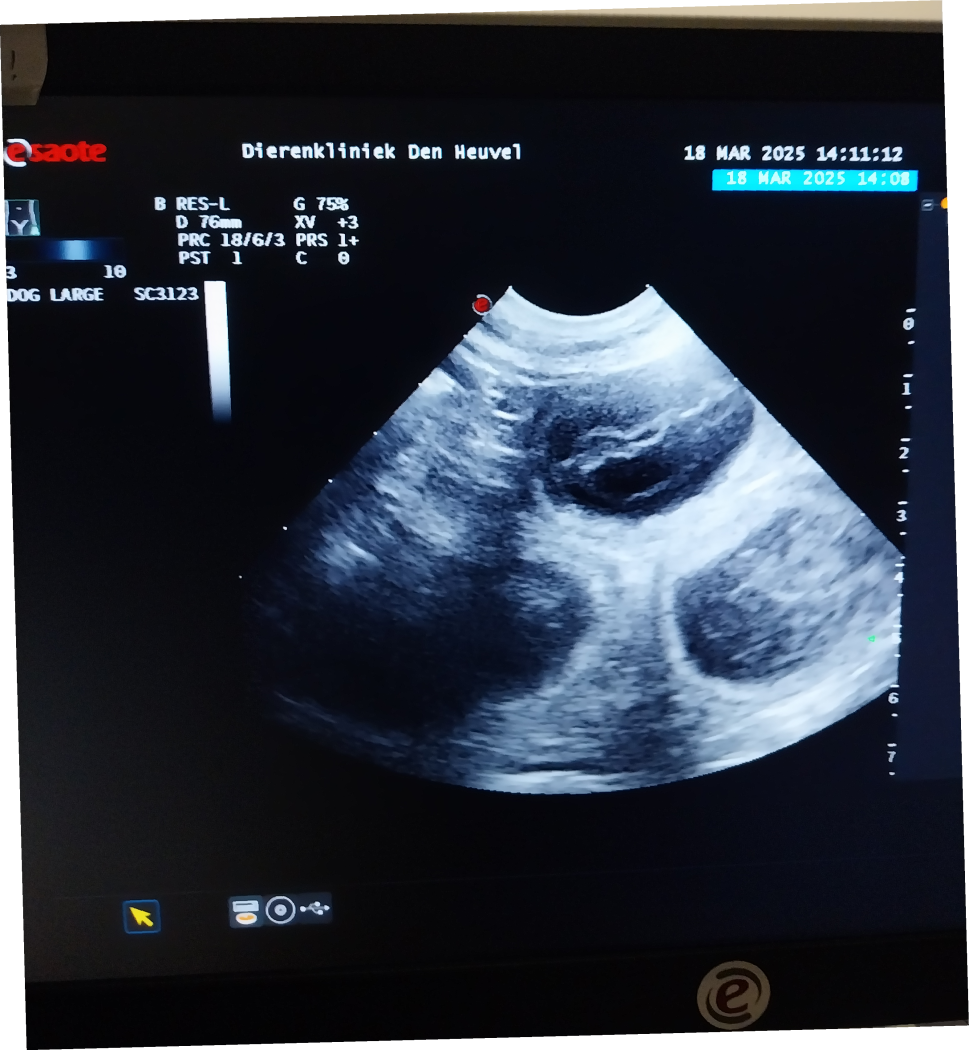

Een echo heeft vandaag bevestigd dat Amra

drachtig is!